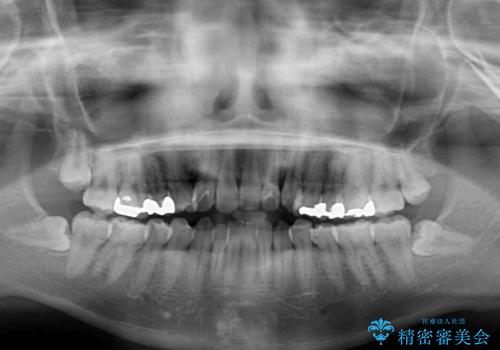

骨格的に下顎が右側に変位しているため、左右の咬み合わせを理想的なものに改善することはできませんが、インビザラインにて歯列を整えることとしました。

骨格的なズレによる左右差は改善できませんでしたが、上下の正中を極力合わせるようにすることができました。